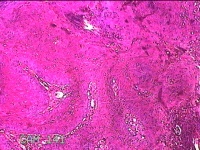

右侧头皮息肉

性别

男

年龄

46岁

临床诊断

一般病史

发现右侧头皮息肉2年余。

大体所见

带皮肤组织2x1.2x0.8cm一块,表面光滑,切面灰白粉红色,质中。

图2